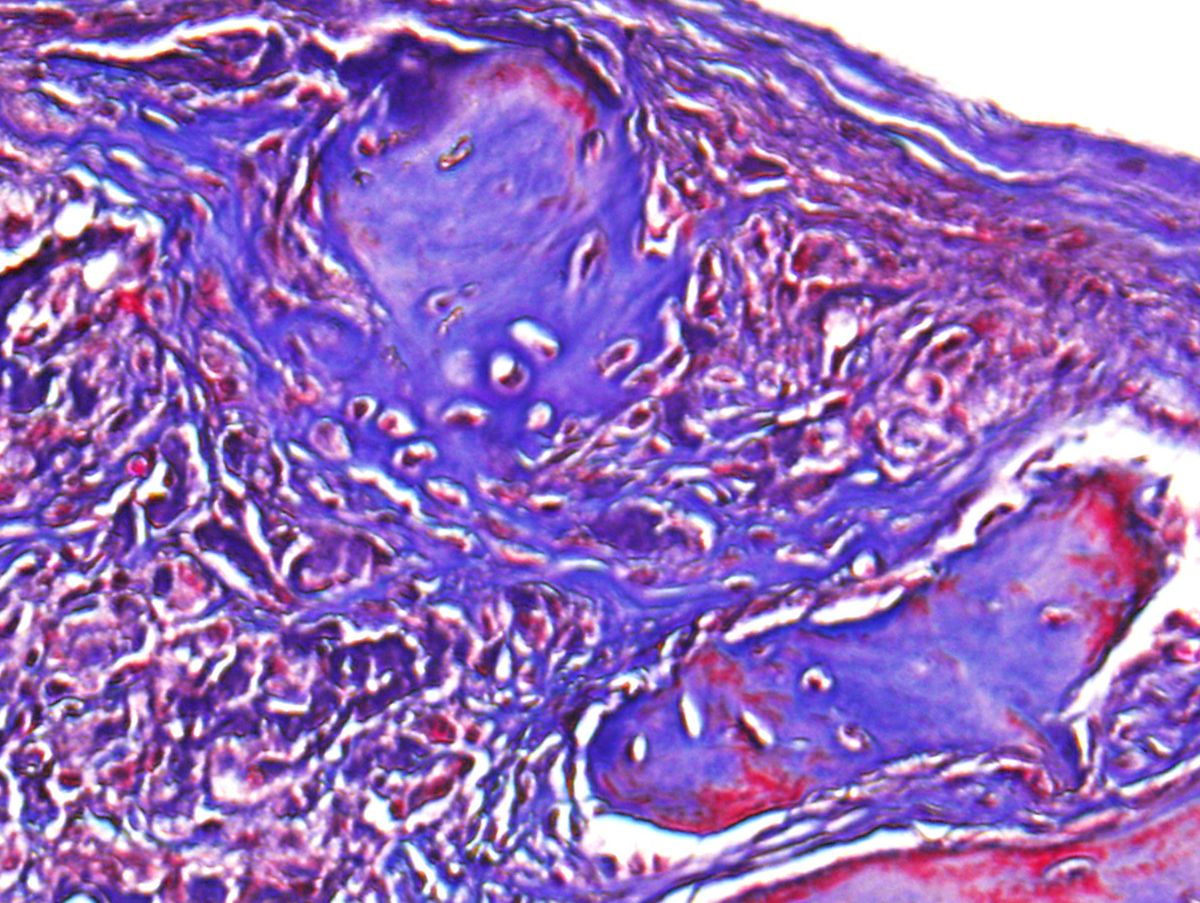

The mouse model had a non-healing skull defect, which the researchers injected with their clay-enhanced hydrogel. After six weeks, they found that the model showed significant bone healing through its own naturally occurring stem cell migration and growth.